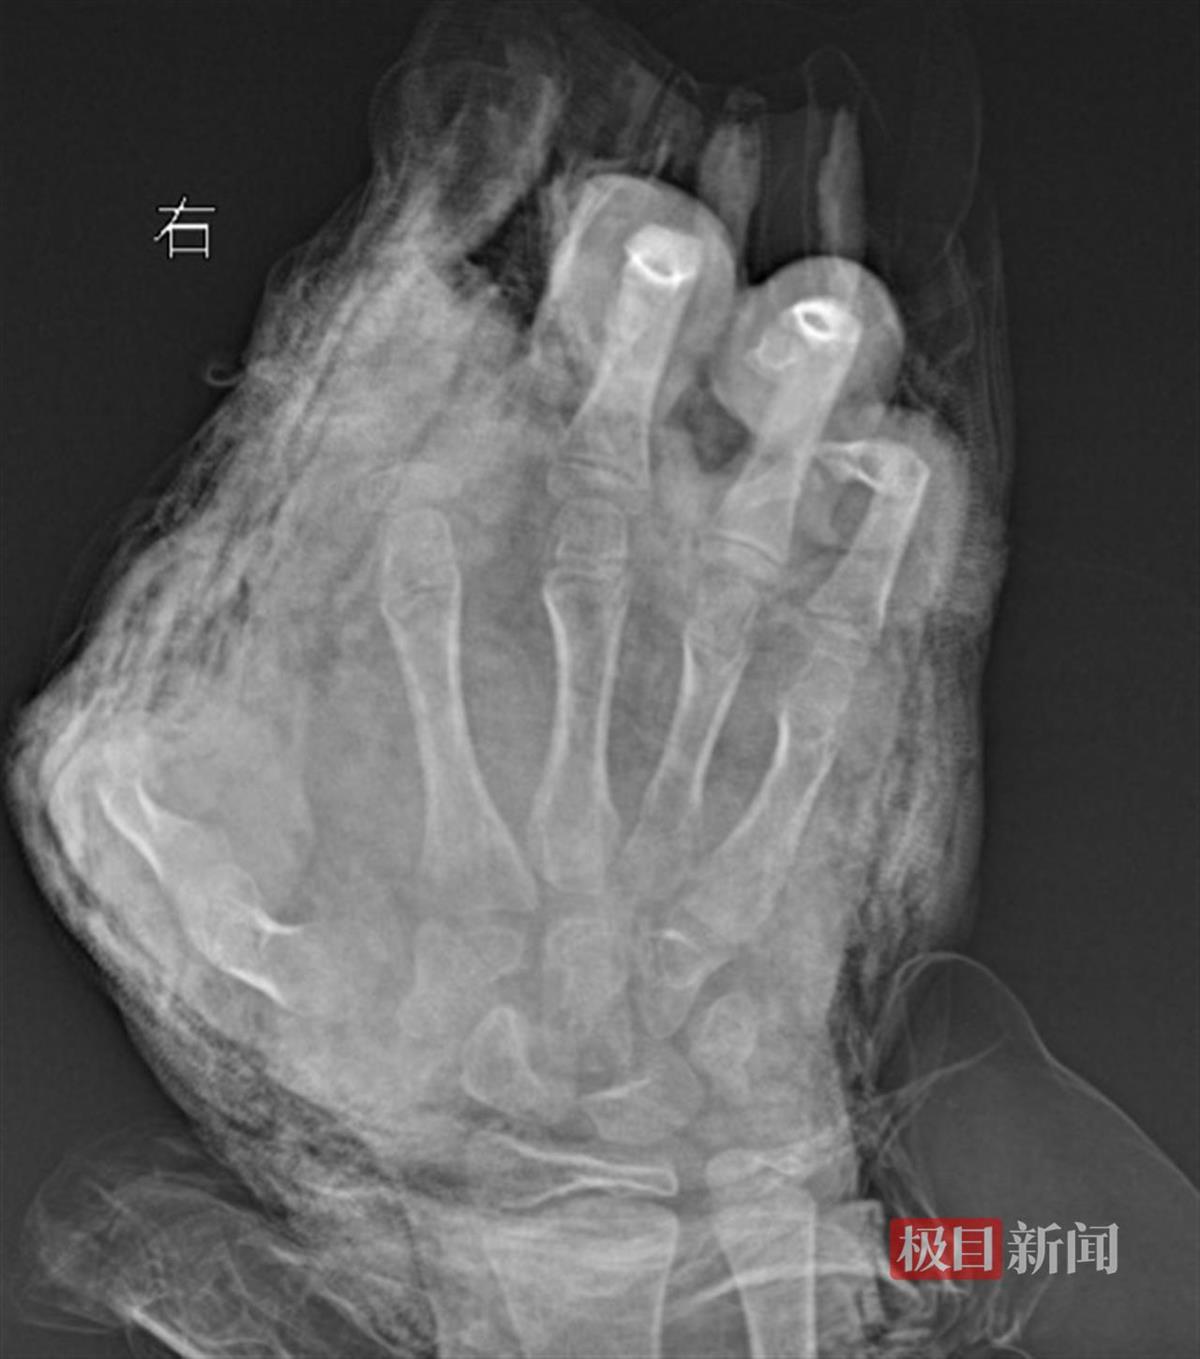

明明右手影像图

“孩子来院时,伤得触目惊心。”武汉市第四医院小儿创伤及矫形中心副主任医师徐剑介绍,初诊时看到明明双手血肉模糊,脸上和胸前均有炸裂伤,右手伤得最重,虎口处的伤口中还嵌入了小石子。经进一步检查发现,明明右手虎口处裂伤至手腕处,右手食指完全离断,拇指前段二分之一处被炸断,中指远节软组织缺损,环指和小指指腹炸伤严重。

徐剑介绍,由于孩子的手掌和手指被炸伤较为严重,离断的食指因为血管和肌腱撕裂严重无法再植。目前还要继续观察伤情,择期进行二次清创及修复手术。